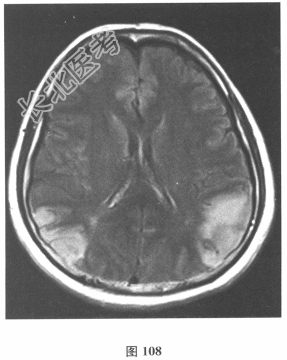

- 简答题2、脑脊液检查:常规、生化均正常,CSF-病毒TORCH(-),抗Hu、Yo、Ri均阴性,OB、MBP正常。血清抗Hu、Yo、Ri均阴性。颅脑MRI显示左颞枕、右顶枕多发长T₁、长T₂信号,Flair高信号,病变累及皮质及皮质下白质,病灶无强化,见图108~图114。)根据颅脑MRI,需要鉴别的疾病应是